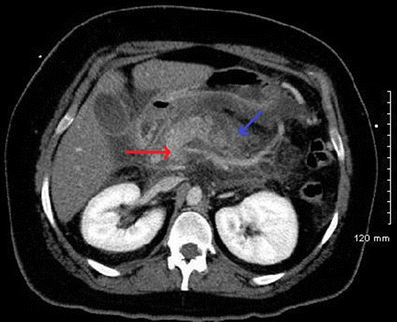

A 23-year-old woman with type 1 diabetes mellitus (hemoglobin A1c 12.7 %) presented with severe abdominal pain, hypotension and tachycardia. Blood glucose was 418 mg/dL, lipase was elevated to 1774 units/L and ionized calcium was 3.2 mg/dL. Her abdominal computed tomography (CT) scan demonstrated extensive necrotizing pancreatitis (Fig. 1). Serum triglyceride (TG) level was 4425 mg/dL. A diagnosis of hypertriglyceridemia-induced pancreatitis was made. After aggressive resuscitation, an insulin drip was initiated and she received a single plasmapheresis cycle, with removal of a thick milky ultrafiltrate (Fig. 2). Serum TG level fell to 484 mg/dL and she was discharged.

CT of the abdomen demonstrating pancreatitis with patchy necrosis (red arrow) and peripancreatic edema and indistinct pancreatic borders (blue arrow).